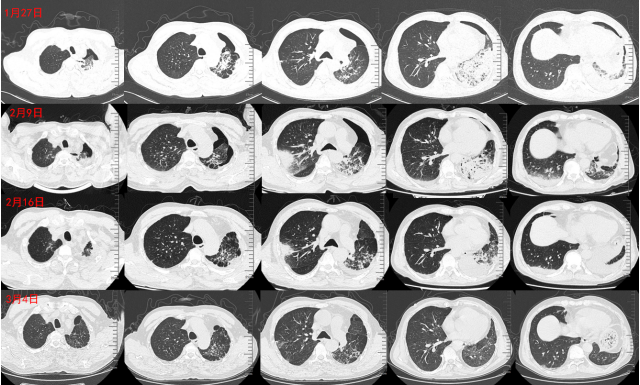

出院后,嘱患者口服泼尼松50 mg qd,并于2周后复查。3月4日患者门诊复诊,自诉呼吸困难、咳嗽咳痰症状明显减轻,复查胸部CT示双侧病灶明显吸收。

回顾患者影像学情况:1月27日患者入院,胸部CT以左肺病变为主,有液气胸表现。2月9日胸部CT可见右肺有大片新发病灶。经过甲泼尼龙治疗,2月16日胸部CT示左肺病灶明显吸收,3月4日门诊复查时可见胸部CT示双肺病灶均明显吸收(图10)

图10  病程中患者影像学变化